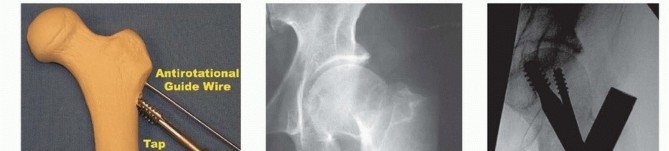

TECH FIG 4 • Landmarks for cephalomedullary nail placement. The iliac crest is marked and the trochanter is outlined. The incision is in line with the femoral shaft and several centimeters proximal to the tip of the trochanter. This can be done by a Smith-Petersen or Watson-Jones approach, as described earlier. An antirotational pin may be used to maintain reduction ( TECH FIG 5B,C). Once reduction has been obtained, the entry reamer is introduced ( TECH FIG 5D). For a short cephalomedullary nail, the entry reamer is all that is needed before nail passage. If a long cephalomedullary nail is being placed, serial reaming can be performed to 1 to 1.5 cm over the desired nail diameter. ### Proximal and Distal Interlocking After the nail is positioned at the correct depth, the guidewire into the femoral head is placed. Multiple fluoroscopic images are needed to make sure the tip of the guidewire is placed within the center of the femoral head for nails with a single screw going into the head. Newer nails with more than one screw going into the head may necessitate adjustments to this technique to allow passage of both screws (such as placing the first lag screw slightly superior to center to allow passage of the second screw inferior to center). A depth gauge is used to check the length of the guidewire. For rotationally unstable femoral neck fractures, an antirotational guidewire or screw can be placed to prevent rotation of the fracture with tapping ( TECH FIG 6A). Many nail systems allow a pin to be placed through a sheath attached to the jig or have an antirotational bar. A reamer is then used to open the outer cortex of the femur and is continued into the head under fluoroscopic guidance. The reamer should be checked during passage to ensure the guidewire is not being driven into the pelvis and the reduction is not lost during reaming. The lag screw is then tapped, and fluoroscopy is again used to ensure the reduction is not lost. The lag screw is placed and fluoroscopy undertaken in multiple views to rule out penetration of the subchondral surface. If a distal interlock is desired, it is then placed. Most nail systems have a set screw that needs to be advanced to give rotational control to the lag screw. If compression is desired, the set screw then needs to be loosened, usually a quarter-turn of the screwdriver, according to the recommendations of the individual nail system being used. As mentioned earlier, appropriate films should be taken with the patient aslee This may include plain films if fluoroscopy is not adequate ( TECH FIG 6B,C). 383

### TECH FIG 6 • A. Antirotational screw is placed in addition to guidewire before tapping when using a sliding hip screw or cephalomedullary nail. B. Preoperative radiograph showing a displaced femoral neck fracture. C. Final intraoperative AP fluoroscopic view showing anatomic reduction with antirotational screw with cephalomedullary nail.